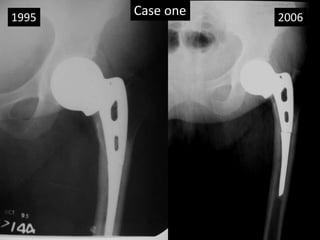

Case one

• 18 years old lady had a puerperal sepsis - 1982

• Acute renal shut down ended up in CRF.

• Had fracture neck of femur -1985.

• AMP was done considering failures of internal

fixation in CRF patients(Past experience of failure

in two cases) and limited life expectancy.

• Had Renal transplant in 1987

• She was 7th case of renal transplant at Choithram.

Case history continue…

• On regular follow up.

• Delivered a baby girl 1991.

• Severe obesity.

• Stem broken noted in 1995 (x-rays)

• Last follow up 2006.

• Had Ca Breast with multiple mets – died 2007.

• No x-ray changes noted between 1995 – 2006.

Case one1995 2006

2006